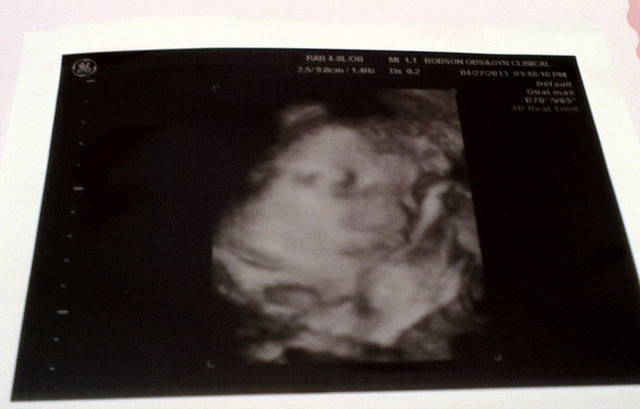

看看一開始產檢醫生幫我拍的照片

章魚妹妹在打呵欠啊

嘴巴張這麼大

還是最後笑起來的比較可愛